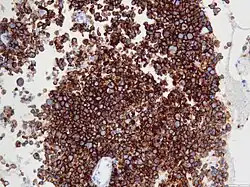

| Micrograph of an anaplastic large-cell lymphoma. H&E stain. | |